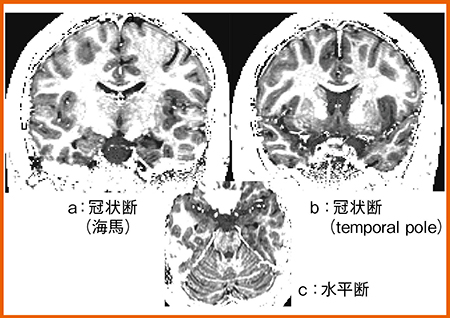

QPM(図5)では,T2強調画像とT2*強調画像で左側海馬に軽度の信号変化を認める。一方,FLAIR画像では同部に明らかな高信号,r1マップでは側頭葉内側から下部にかけて明瞭に低信号が認められた。また,ミエリンマップでも海馬付近に低信号が認められ,髄鞘の低下が示唆された(図6 a)。側頭極レベルではさらに信号が低下し,左側のミエリン密度の低下と菲薄化が確認できた(図6 b)。FDG-PETでも,左側皮質側にFDG集積の低下,アシンメトリーマップでもFDG低下が確認できたことから,QPMは神経変性を表していると考えられる。

QPMでは各種パラメータ画像で病変のコントラスト変化を網羅的に評価できるため,診断能の向上が期待できる。また,ミエリンマップなどの組織特異的な情報も非常に有用である。ただし,皮質構造などの詳細な形態評価には,空間分解能向上が必要であり,撮像高速化と併せて今後の課題である。

図6 症例2:ミエリンマップ